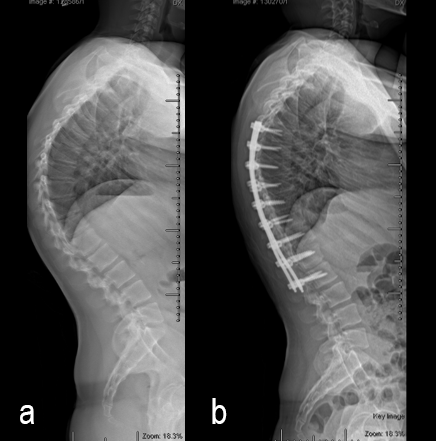

A 19-year-old man with colon cancer was admitted to the spine clinic with pain and progressive kyphosis (Fig 5a). Preoperative CT imaging (Fig 5b) showed a residual mass abutting the superior mesenteric artery.

Surgery was undertaken with TriALTIS™ posterior spinal instrumentation system from T5 – L1 to correct and support the kyphotic deformity (Fig 6a-b). The upper and lower instrumented vertebrae were selected to allow symmetry of fixation above and below the apex of the kyphotic curve. Care was taken not to overcorrect the hyperkyphosis given the abdominal mass abutting the superior mesenteric artery. During surgery, multiple sequential reducers were used to achieve cantilever reduction of the deformity (Fig 7).